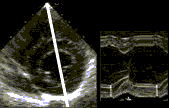

Il formato M-mode (diagramma spazio/tempo) illustra, nel modo più semplice ed intuitivo

ed in una singola immagine, l'ispessimento sistolico

parietale. Tuttavia la valutazione della funzione sistolica è

Il Panoramic M-mode, come le tecniche precedenti, riassume in una singola immagine,

l'ispessimento parietale dei vari segmenti di parete del ventricolo sinistro.